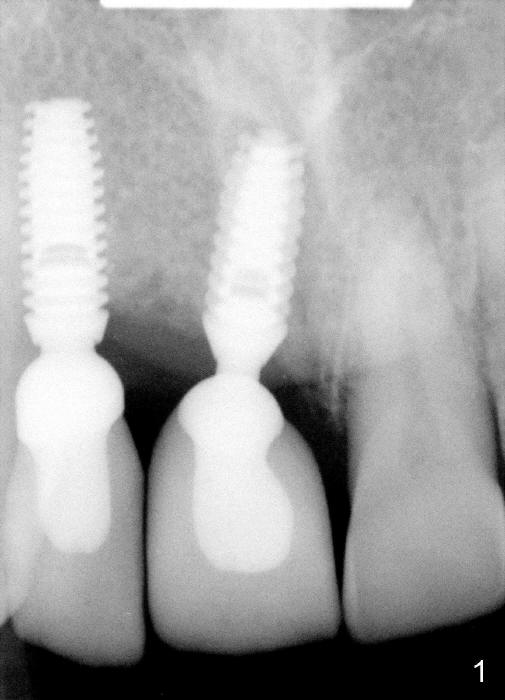

IACs were seated for Sergio last week as shown by Fig.1.  A few days later, he reported that the crown(s) was/were loose.  Did I show you in web how to tell whether an IAC or abutment is completely seated?  Where can we find the page?

Why were these two IACs in fact not completely seated indeed?  Can you look at the X-ray with critical thinking?  Is there anything wrong with the X-ray, even though it was taken by the doctor?

-the abutment/crown unit is tapped into the implant with two visible threads instead of three

-the latter indicates that the abutment is completely seated

Is there anything wrong with the x-ray? Implant threads (outside) which are not distinct (blurred), suggests that the sensor was not placed parallel to the upper anterior jaw (implants) in Fig.1.  The threads seen across the inside of the implant well are also difficult to comprehend.  In contrast, the X-ray taken today is much better (Fig.2).

Doctor Wei:  About the old X-ray, I think it shows the sensor was not paralleled with number 8 tooth, that is why number 8 implant root threads look blurry  on the X-ray, so it is not very clear if there are two threads space or three. If it was two, that means the IACs were completely seated.

If there were two threads space between the IAC and implant well, but crown still loosened, then I think patient probably loosened this crowns by grinding teeth at night.